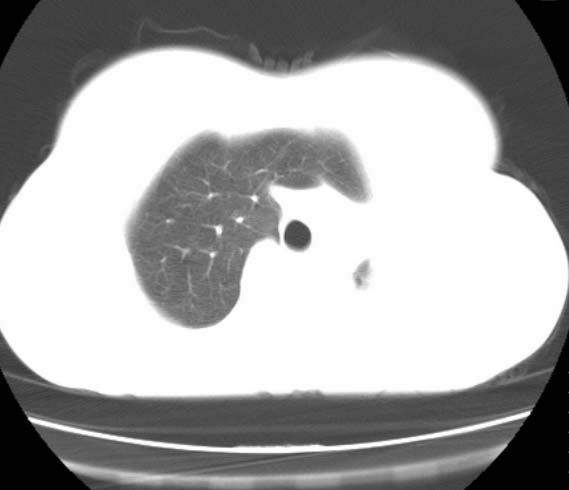

标题: CT25648:求教:是肺发育不全还是结核?

女  20岁。一月前咳血,诊“肺结核”抗痨治疗一月后,咳血停止,现复查。病人精神好。前后ct片对比未见明显变化。既往体检“正常”

1)考虑左肺结核并肺不张、支气管扩张。2)纵隔疝。

考虑左肺结核,左肺毁损,纵膈左偏,既往体检正常不可靠,tb一个月也不会这个样子的,有钙化,应该病程较长,冰冻三尺非一日之寒!

左肺发育不全。